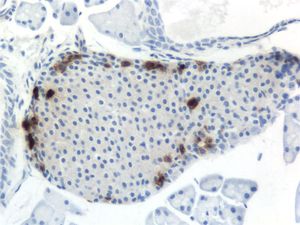

건강한 성인의 췌장에는 약 100만~300만 개의 랑게르한스섬이 분포하며, 각 섬은 지름 0.1mm~0.2mm 정도이다.[42]:914[5]:928 섬들은 얇은 섬유성 결합 조직 캡슐로 둘러싸여 있으며, 췌장의 다른 부분과 연결되어 있다.[42]:914:928

랑게르한스섬은 최소 5가지 유형의 내분비 세포로 구성되어 있으며, 각 세포는 특정 호르몬을 생성하여 혈류로 직접 분비한다. 이 세포들은 다음과 같다:[43]| 세포 유형 | 분비 호르몬 | 비율 |

랑게르한스섬 내 세포 분포는 종에 따라 다르다.[44][45][46] 설치류는 베타 세포가 중심부에, 다른 세포들이 주변부에 분포하는 반면, 사람은 알파 세포와 베타 세포가 섬 전체에 비교적 고르게 분포한다.[44][46] 조류는 알파 세포가 중심부에 위치하는 경향이 있다.